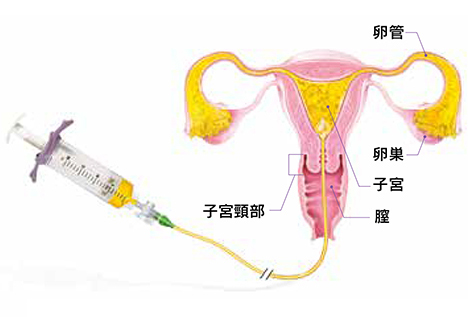

リピオドール®を使用した子宮卵管造影(HSG)の手順

提供: Dr. Kim Dreyer, Amsterdam University Medical Center (Netherlands)